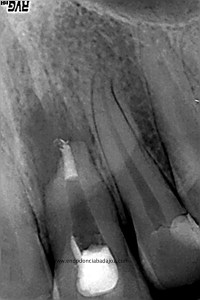

Nos refieren a una chica para retratarle un 2.1, le hicieron un tratamiento de conductos hace unos 5 años y obturaron con pasta. No se recomiendan una obturación con pastas por que no van a conseguir una obturación tridimensional y hermética, y en ocasiones pueden reabsorberse, con lo cual, está contraindicada la obturación solo con pastas.

La paciente presenta un lesión periapical y una tumefacción fluctuante, decidimos retratar.

Intentamos eliminar toda la pasta de las paredes, determinamos el diámetro apical superior a 80, con lo que decidimos actuar colocando una barrera de M.T.A. (Trióxido Mineral Agregado) y hacer un backfilling con gutapercha inyectada.

Lo realizamos en dos sesiones, algo discutido entre compañeros, pero que en este caso, no dudo en absoluto,  pues presentaba una reabsorción apical. Incluso, a la hora de colocar el H de Ca, la medicación intraconducto elegida, decidimos extruirla.

Colocamos la barrera apical verificando que conseguíamos un buen sellado:

(Rx Mesioradial)                                                 (Rx Ortoradial)